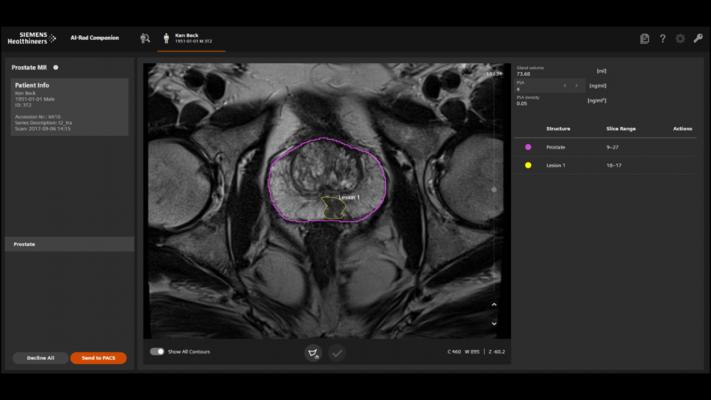

August 19, 2020 — The Food and Drug Administration (FDA) has cleared two additional Siemens Healthineers artificial intelligence-based software assistants in the AI-Rad Companion family. Both new software assistants free radiologists from routine activities during magnetic resonance imaging (MRI) examinations. The AI-Rad Companion Brain MR for Morphometry Analysis automatically segments the brain in MRI images, measures brain volume, and marks volume deviations. The AI-Rad Companion Prostate MR for Biopsy Support automatically segments the prostate on MRI images and enables radiologists to mark lesions, facilitating targeted prostate biopsies.

The AI-Rad Companion Prostate MR for Biopsy Support automatically segments the prostate and marks the organ’s outer contour in seconds rather than minutes, as is the case with manual segmentation. The radiologist then simply marks the suspect areas and sends the annotated MRI images to the urologist for fusion with ultrasound images during the biopsy. These targeted, MRI-supported biopsies can help the urologist detect significant prostate carcinomas and improve patient care.